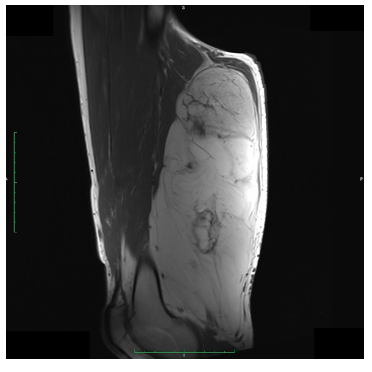

Radiographic imaging is used to help form a diagnosis. These include X-Ray, MRI, CT and Bone Scans

An example of MRI is shown.